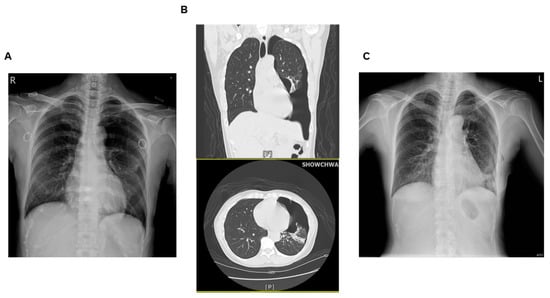

2.1. Case 1

2.2. Case 2